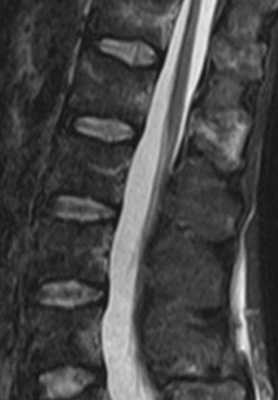

Изменения сигнала по типу MCh2 характеризуются гиперинтенсивным сигналом на T1- и Т2-ВИ и обусловлены жировой дегенерацией костного мозга (рис. 2). Гистопатологический анализ демонстрирует разрушение КПП и образование грануляционной ткани без гиперваскуляризации, замену костного мозга жировой тканью [2, 12].

Рис. 2. Изменения на МРТ по типу MCh2. 1 — гиперинтенсивный сигнал на T1-ВИ; 2 — гиперинтенсивный сигнал на Т2-ВИ; 3 — гипоинтенсивный сигнал в режиме подавления сигнала от жира (STIR).